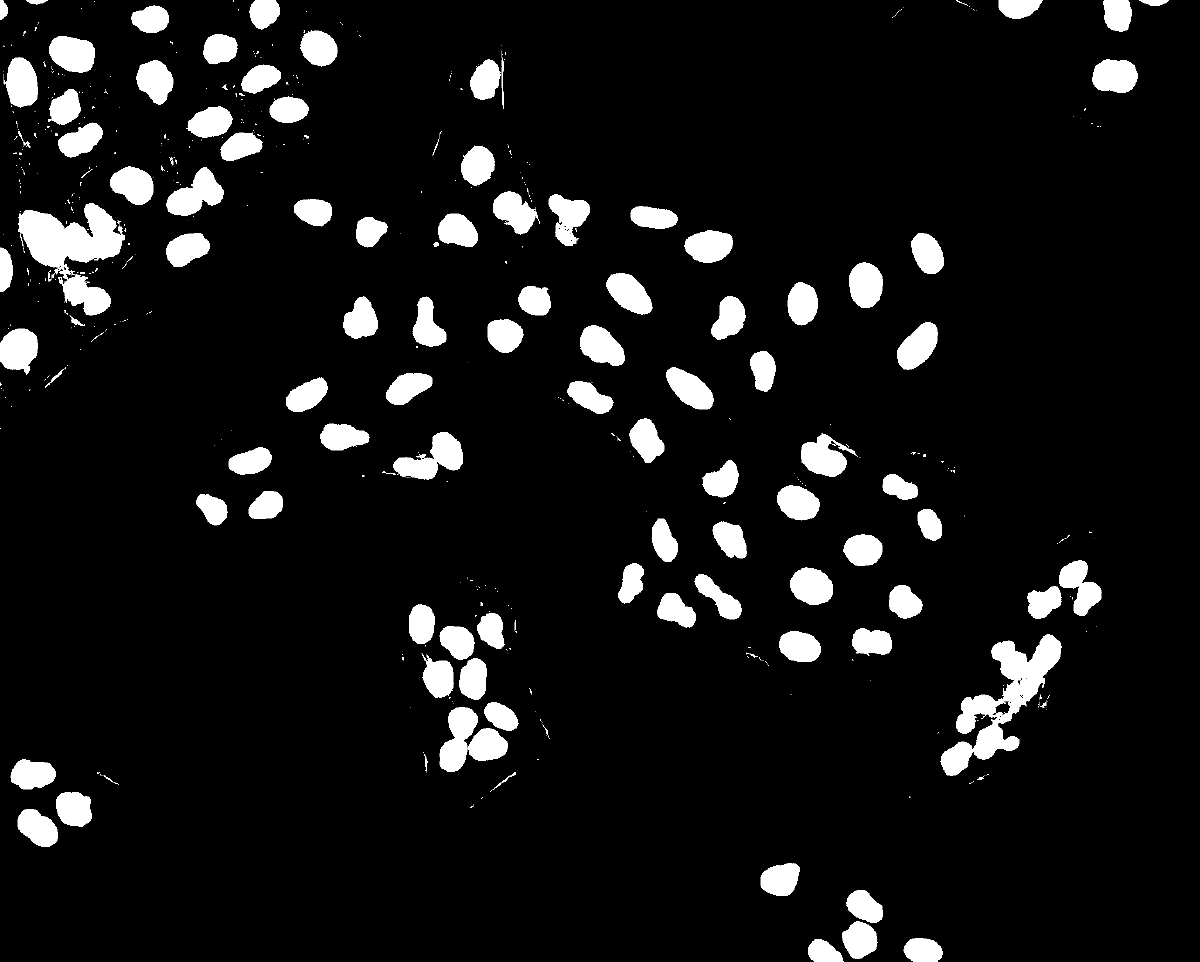

Fj #9 Gauss + Otsu + Open + WS ★

Fj Nuclei Segmentation Result 103 nuclei — Osteosarcoma_01.tif

103 nuclei detected · Approach #9